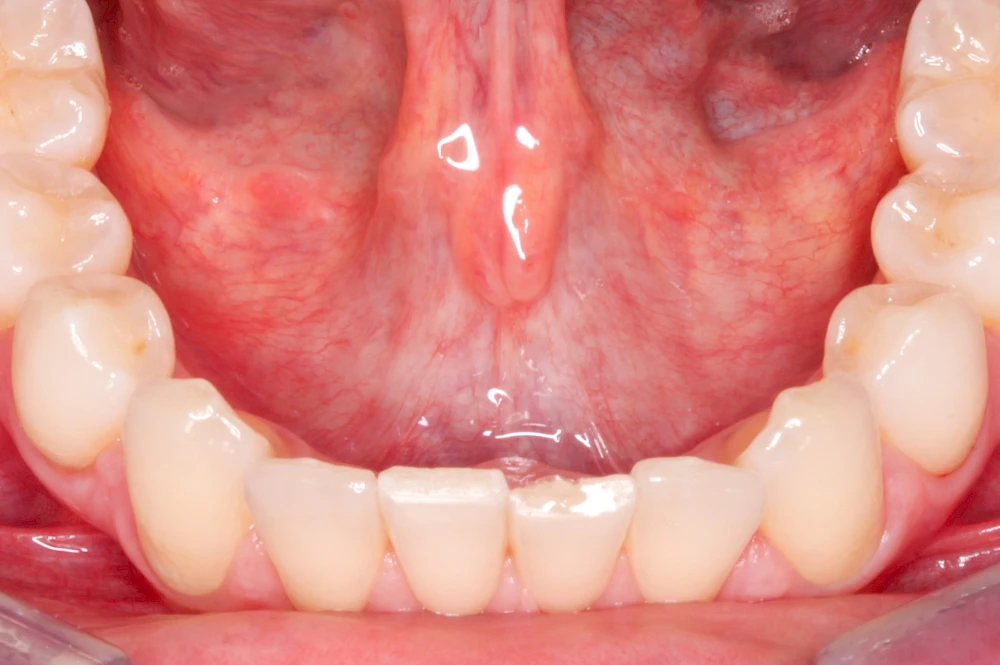

Schleimhäute

Schleimhäute kleiden Körperhöhlen aus – auch den gesamten Verdauungstrakt, beginnend mit dem Mund. Schleimhäute sind im Vergleich zur äußeren Haut viel dünner und weniger widerstandfähig. Der Aufbau ermöglich andererseits hochelastische Bewegungen. Lediglich die Zungenoberfläche, das Zahnfleisch und der Bereich des harten Gaumens ist etwas verstärkt (verhornt), da diese mechanisch z. B. beim Essen stärker beansprucht werden.

Die oberste Hautschicht der Schleimhaut wird Mukosa genannt (mucus – Schleim). Der Name leitet sich ab durch die Vielzahl an Speicheldrüsen (siehe unten), die direkt unter der Oberfläche liegen und mit Speichel und Schleimstoffen die Oberfläche angenehm elastisch, feucht und gleitfähig halten.

Im Vergleich zur äußeren Haut fehlen Haare, Talgdrüsen und Farbstoffe (Pigmente). Die rötliche Färbung ergibt sich aus der guten Durchblutung.

- Unterzungenspeicheldrüse (Glandula Sublingualis)

Während die Ohrspeicheldrüse überwiegend dünnflüssigen Speichel vor allem zu den Mahlzeiten über einen kleinen Ausgang im Bereich der Wange etwa gegenüber den großen Backenzähnen (Molaren) absondert, ist der Speichel der Unterkiefer- und Unterzungenspeicheldrüsen eher dickflüssig und wird überwiegend unstimuliert – also zwischen den Mahlzeiten – über die sogenannten Carunceln unter der Zunge, abgesondert.